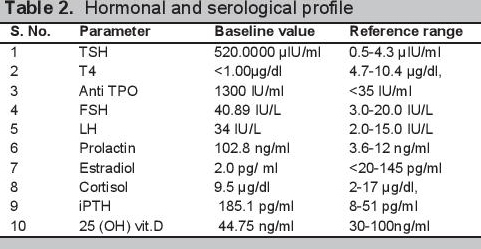

Biochemical evaluation revealed microcytic hypochromic anemia, hypocalcemia and hyperphosphatemia (Table 1). The hormonal investigations were done through chemiluminescence immunoassay by Abbott ARCHITECT i1000sr immunoassay analyzer USA using fasting plasma sample which revealed elevated parathormone level, autoimmune hypothyroidism, hypergonadotropic hypogonadism along with raised prolactin (Table 2). Roentgenographical assessment revealed bilateral short 3rd, 4th and 5th metacarpals and metatarsals with positive Archibald sign [Figure 3a,b] while the rest of the skeletal survey was normal. Ultrasonography of the abdomen showed streak ovaries along with pre-pubertal uterus. Her karyotype showing 45 (X,O) confirmed the diagnosis of Turner syndrome. Electrocardiography, 2D echocardiography and pure tone audiometry were unremarkable while thyroid ultrasonography revealed hypo-echogenicity of the thyroid gland.

Click here to download Table 2

Table 2.Hormonal and serological profile

After 2 months of therapy, the patient showed significant clinical and biochemical improvement. On follow up visit after 2 month, her hemoglobin was 11.2 gm/dl. Her thyroid functions were improved with TSH 6.4329 μIU/m and T4 5.85 μg/dl along with normalization of serum prolactin (S. Prolactin: 5.5 ng/ml). The patient became normocalcemic and normophosphatemic with serum calcium 9.2 mg/dl and serum phosphorus 6.47 mg/dl and her parathormone level was 74.2 pg/ml.

PHP is a heterogeneous disorder with a variety of manifestations. The prevalence of the disorder is about 0.79 per 100,000.[1] It was the first hormone resistance syndrome ever described. The first description of pseudohypoparathyroidism with Albright hereditary osteodystrophy was made in 1942 by Fuller Albright.[5] In his original work, Albright described a person with hypocalcemia and hyperphosphatemia with normal renal function who had no calcemic and phosphaturic response to bovine parathyroid extract as compared to hypoparathyroid patients, hence the concept of hormone resistance came into being.[5] Later on, with the discovery of the PTH receptor and its mechanism of action, the basic pathophysiology of the disorder was described and the syndrome was further subdivided into various types.[1] The primary pathological mechanism was described as a GNAS mutation which leads to defective activity of Gsα (stimulatory subunit of G protein coupled receptors).[1] PHP has various manifestations due to the involvement of maternal imprinting of the genes.[1] PHP 1a is characterized by parathormone resistance (elevated PTH in spite of hypocalcemia and hyperphosphatemia; poor cAMP and phosphaturic response to exogenous PTH administration) along with features of Albright’s hereditary osteodystrophy (AHO), characterized by brachydactyly, rounded face, short stature, central obesity, subcutaneous calcifications in conjunction with variable mental retardation.[1] Together with variable PTH resistance, resistance to other hormones operating through G protein coupled receptors can also be present in PHP.[1] The patient in the present case had short stature, a round face, brachydactyly [Figures 1 and 2a,b] and elevated PTH in spite of hypocalcemia and hyperphosphatemia (Table 1). Along with these features, the patient also had delayed puberty and no development of secondary sexual characteristics due to hypergonadotropic hypogonadism. Her skeletal survey showed specific changes associated with AHO such as short 3rd, 4th and 5th metacarpals with short distal phalange of her thumb but the absence of heterotropic calcification.

So far in medical literature, only one case of pseudohypoparathyroidism 1a with Turner syndrome has been described.[8] Another case of pseudopseudohypoparathyroidism with Turner syndrome and one case with pseudohypohyperparathyroidism have been reported.[9][10] The only case of pseudohypoparathyroidism with Hashimoto’s thyroiditis with Turner syndrome was described by Wen Heng-Zeng et al., in 2014 in which they described the case of a 16-year-old female presenting with short stature. On examination, round chubby face, short neck, short stature and obesity were observed. Biochemical investigations revealed elevated parathormone, thyroid stimulating hormone (TSH), prolactin, follicle stimulating hormone (FSH), antithyroid peroxidase antibody and anti-thyroglobulin antibody levels. The radiological examination showed delayed bone age, immature uterus along with shortening of metacarpals and metatarsals of the 3rd, 4th and 5th digits. Karyotyping revealed 46, X, i (Xq10), while molecular analysis unmasked a silent codon change in exon 5 of GNAS (ATC → ATT, Ile).[8]

In our case, the patient had similar finding on clinical examination except for obesity and heterotrophic subcutaneous calcifications. Biochemical findings were also similar except the patient had microcytic hypochromic anemia. Radiological findings of our case completely correlate with the findings described by Wen Heng-Zeng. Karyotype of our patient showed complete absence of one X chromosome [45,XO].